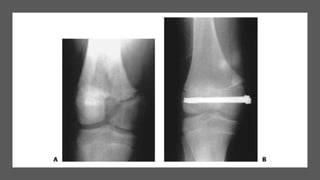

Type 4

• Type IV fractures are effectively vertical shear

fractures, extending from the articular surface

to the metaphysis.

• These fractures are important because they

disrupt the articular surface, violate all the

physeal layers in crossing from the epiphysis to

the metaphysis, and, with displacement, may

result in metaphyseal–epiphyseal cross union

which almost invariably results in subsequent

growth disturbance.

• This fracture pattern is frequent around the

medial malleolus ,lateral condyle of humerus.

• In type 4, treatment principles

include obtaining anatomic

reduction and adequate

stabilization to restore the

articular surface and prevent

metaphyseal–epiphyseal cross

union , to prevent subsequent

growth disturbances.